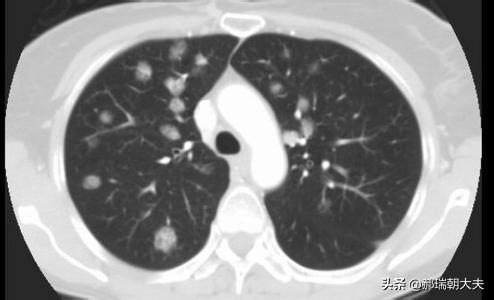

Il existe des nodules pulmonaires multiples et solitaires, et les nodules pulmonaires multiples sont souvent observés à la suite d'une tuberculose ou d'une pneumoconiose, qui sont toutes plus faciles à diagnostiquer avec une anamnèse typique ou une anamnèse du lobe gauche. Les nodules dont nous parlons généralement sont des nodules pulmonaires isolés.

Les examens médicaux étant de plus en plus fréquents, les nodules pulmonaires sont de plus en plus souvent détectés. Les nodules pulmonaires sont un terme d'imagerie, et la définition d'imagerie d'un nodule pulmonaire est une petite lésion bien définie qui est complètement entourée par le parenchyme pulmonaire (Diamètre ≤30mm). La morphologie des nodules est classée comme solide ou sub-solide ; les nodules sub-solides sont eux-mêmes classés en nodules de verre dépoli et en nodules partiellement solides. Les lésions de plus de 30 mm de diamètre sont des masses plutôt que des nodules et ont une probabilité plus élevée d'être malignes.

Environ 99 % des nodules pulmonaires sont des lésions bénignes.Les causes les plus fréquentes sont les granulomes infectieux et les tumeurs bénignes (par exemple, les tumeurs malignes pulmonaires), et parfois les lésions vasculaires et inflammatoires.Environ 1 % des nodules pulmonaires sont malins.Les causes courantes des nodules pulmonaires malins sont le cancer primitif du poumon, les métastases pulmonaires et les tumeurs carcinoïdes.

La plupart des nodules pulmonaires ne peuvent pas être éliminés par la prise de médicaments.Très peu de nodules inflammatoires peuvent être résorbés par des anti-inflammatoires oraux. La prise en charge clinique des nodules pulmonaires dépend de la forme et de la taille du nodule, et différents plans de prise en charge sont élaborés. En général, il est recommandé de suivre régulièrement la plupart des nodules pendant 3 mois, 6 mois, 9 mois ou 1 an (en fonction de la forme et de la taille du nodule). Un très petit nombre de nodules présentant des caractéristiques malignes évidentes peuvent faire l'objet d'une résection chirurgicale.